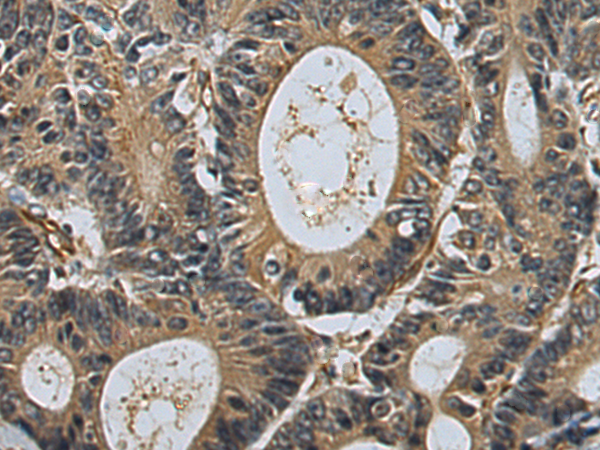

分类: 科研抗体货号: P09349别名: G5; BAT4; D6S54E; ANKRD59; GPATCH10应用: IHC反应种属: Human, Mouse